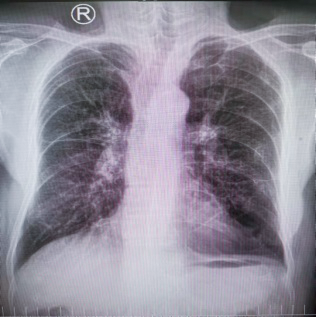

最近,西安高新医院耳鼻喉科就接诊了这样一位老者。老人肺功能严重受损,稍活动就会呼吸困难。来西安高新医院急诊前,老人因为声音嘶哑在外院被诊断为「声带肿物」,但因手术麻醉风险高,多次就医无果。

患者多年慢阻肺病史,肺功能极重度减退,伴有呼吸衰竭,术中可能出现肺通气不良、术中出血以及手术时间较长等情况均可加重呼吸衰竭,极易导致突发意外情况如心跳呼吸骤停等。